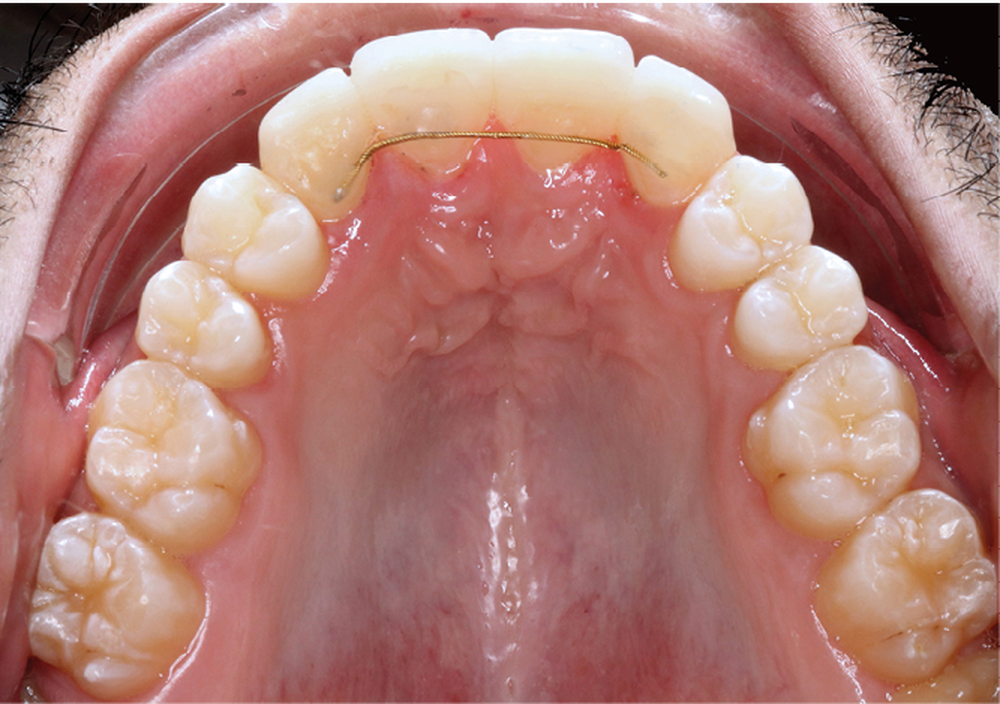

Une fois la croissance alvéolaire terminée, le patient est réadressé à son chirurgien-dentiste pour définir précisément, à l’aide d’une prévisualisation informatique (Digital Smile Design), quelle position dentaire et gingivale est recherchée pour les quatre dents antérieures (fig. 4 a,b) [4]. Le torque et le tip sont particulièrement importants à corriger dans cette phase de reprise de traitement (de quelques mois) car la position des collets et la conservation tissulaire en dépendent fortement.

Les restaurations composites transitoires réalisées au cours du premier traitement cherchant à restaurer l’esthétique de 12 et 22 masquent l’asymétrie de correction des axes radiculaires. La lecture des informations du deuxième et du troisième ordre est ainsi faussée par l’anatomie coronaire perturbée. Une individualisation par plicature est donc nécessaire pour s’approcher au mieux de la prévisualisation, avec pour seuls guides les axes radiculaires radiologiques et la position des collets souhaités (fig. 4a,b).